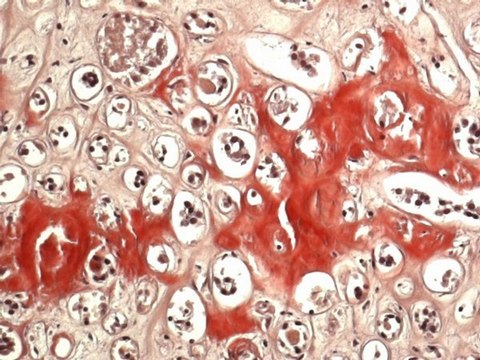

The Congo Red staining kit - Kit for the detection of amyloid acc. to Highman, is used for human-medical cell diagnosis and serves the purpose of the histological investigation of sample material of human origin for example histological sections of e. g. the kidney, the intestine, or the liver.

This Congo red staining kit contains all the reagents necessary for staining amyloid in histological tissues. Amyloid is a homogenous structure made up of protein fibrils (each between 8 and 15 nm in diameter) that can be stained eosinophilically, which e. g. in the case of amyloidosis forms deposits in the intercellular space. All deposits of amyloid contain similar protein fibrils that are resistant to the body′s natural defence mechanisms and that once they have formed cannot be eliminated.The Congo red staining principle is based on the formation of hydrogen bridge bonds with the carbohydrate component of the substrate. Congo red is an anionic dye and is capable of depositing itself in amyloid fibrils, which then exhibit a conspicuous dichroism under polarized light. The tissue stained with Congo red appears orange-red under the transmitted-light microscope; under polarized light, however, the amyloid deposits show up as brilliant green double-refraction images against a dark background. Other structures also stained by Congo red, e. g. collagen, however are not visualized under polarized light. Staining may be technically difficult when the paraffin sections used are too thin (<5 μm) or when the tissue is too strongly over-stained.

Suitability for microscopypasses testAmyloidpink to red; in polarized ligt green metachromasisNucleidark blueConnective tissuelight red